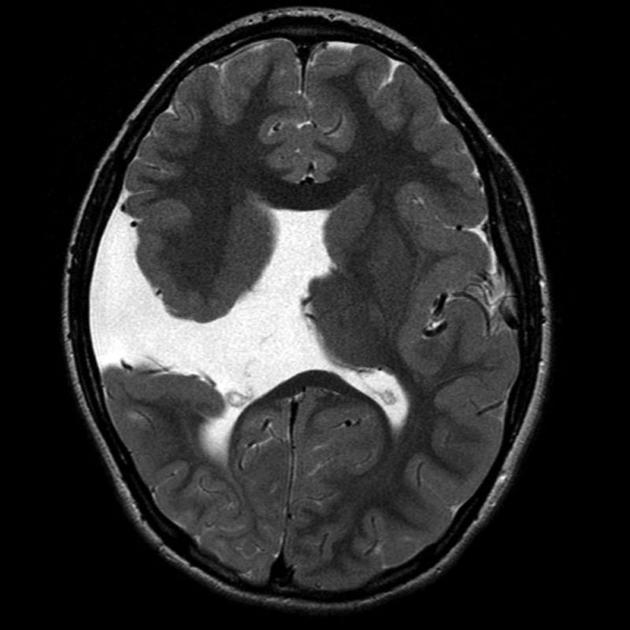

Diagnosis?

Chiari II.

Findings on antenatal ultrasound: banana cerebellum sign, lemon sign.